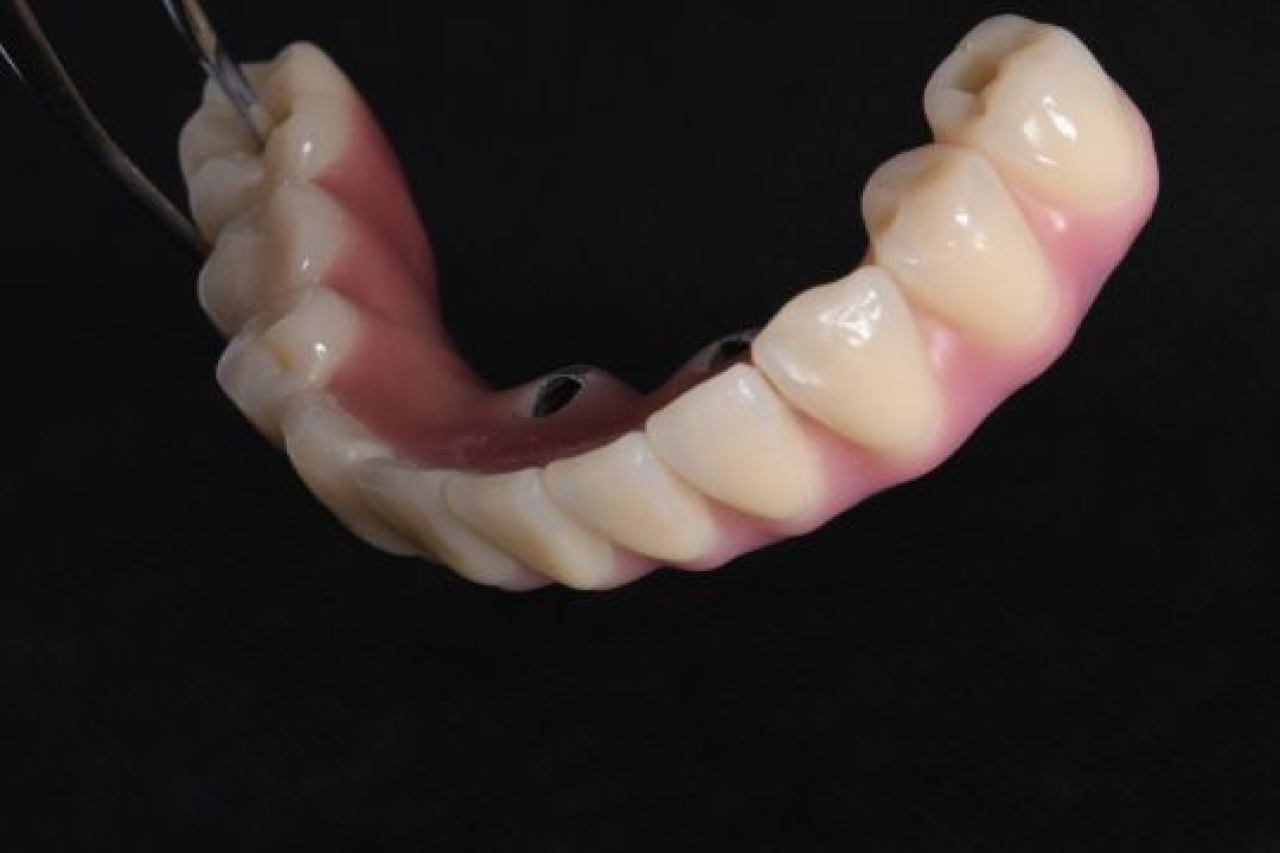

Dentalna implantologija je grana dentalne medicine koja objedinjuje znanje iz kirurgije, parodontologije i protetike i bavi se ugradnjom implantata u bezubu kost gornje ili donje čeljusti.

Marković Dental Clinic koristi najstariji, najistraživaniji i najkvalitetniji sustav dentalnih implantata Švedskog proizvođača Nobel Biocare.

All On 4 i All On 6 fiksni mostovi na 4-6 implantata, omogućavaju da se brzo, ekonomično i efikasno pacijentu od bezube čeljusti omogući mastikatorna i estetska funkcija.